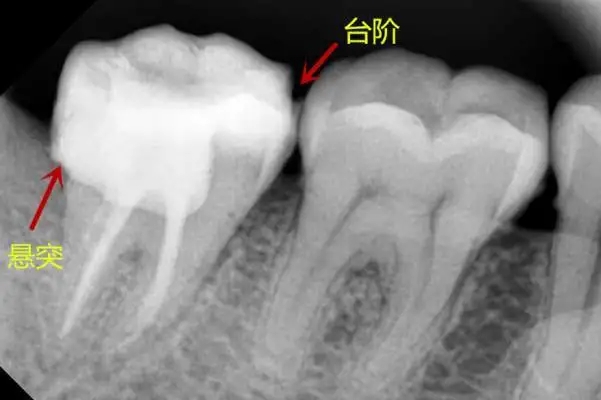

8.悬突

因为补牙引起。补牙分为窝洞制备和填充两个步骤,在填充时如果补牙的邻面充填物不光滑并有突起,就会刺激牙龈引起炎症,从而会引起塞牙。